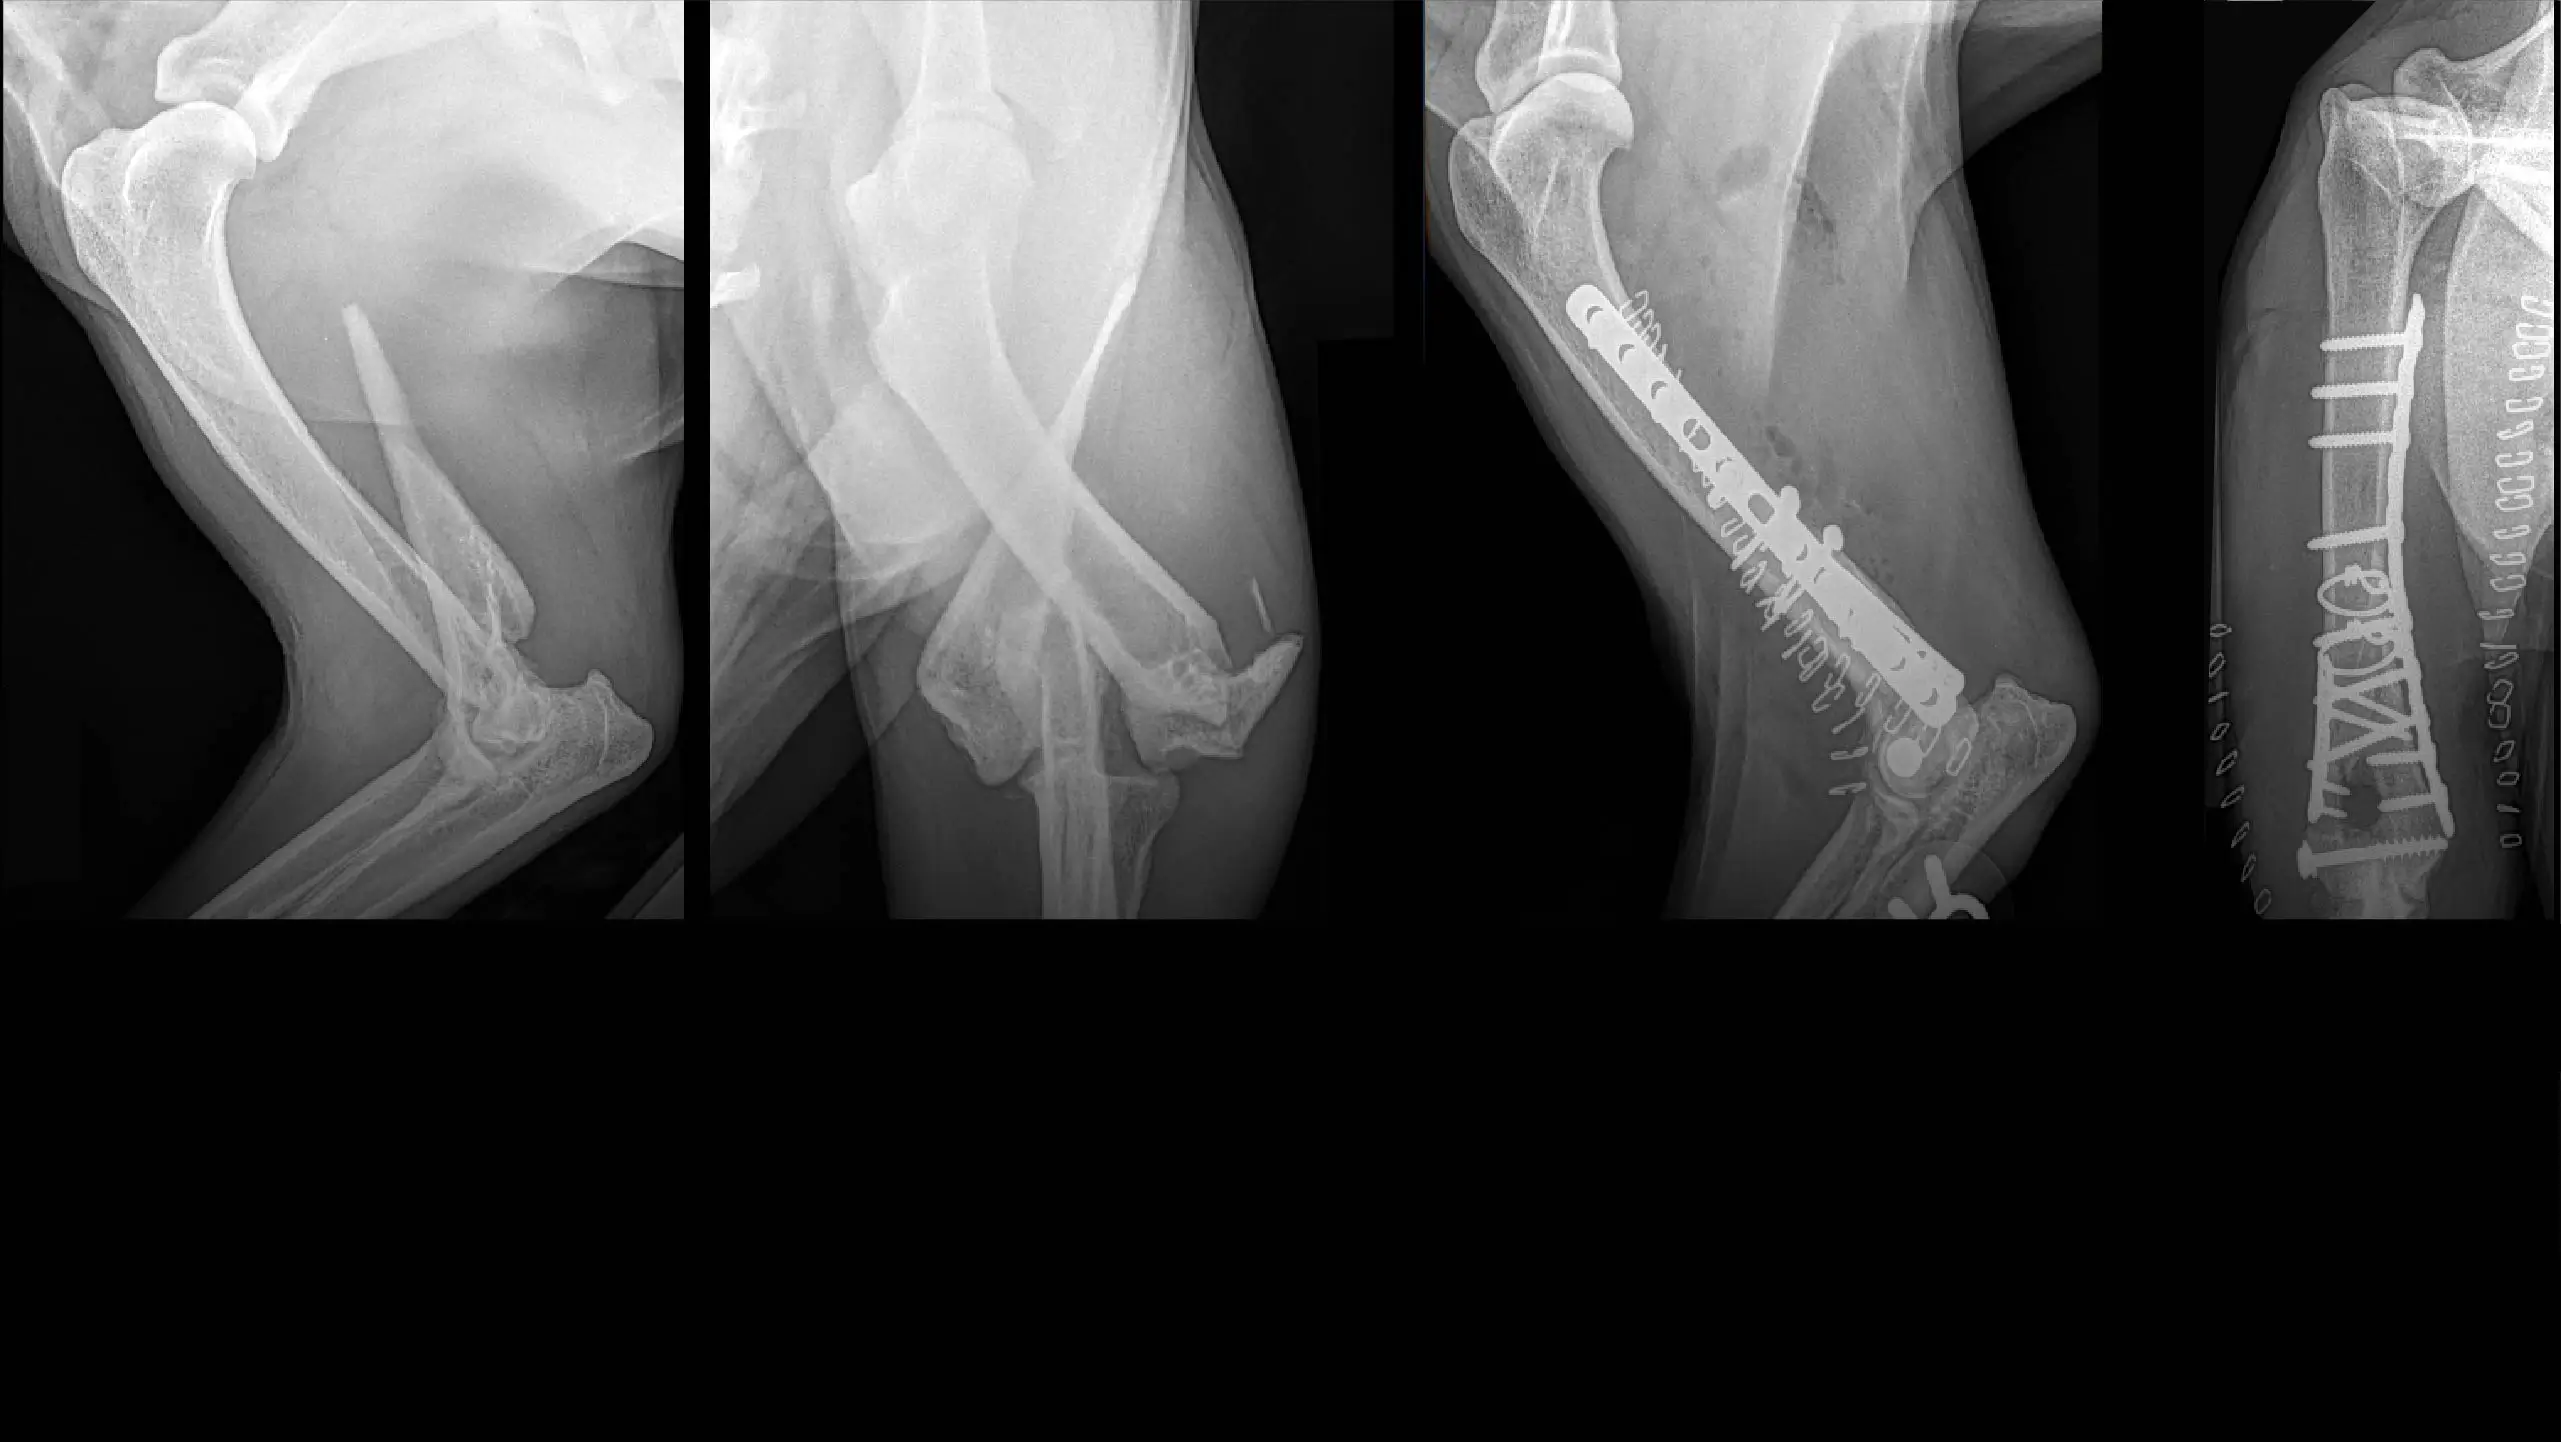

Hip Dysplasia

Distal Femoral Osteotomy for Comprehensive Treatment of Medial Patella Luxation

Three-Dimensional Printed Patient Specific Guides for Acute Correction of Deformities